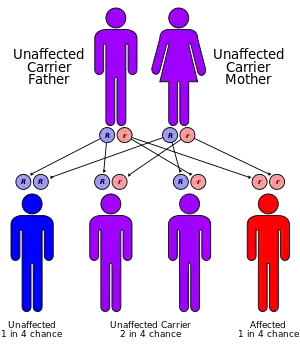

| Causes | Autosomal recessive growth hormone receptor gene mutation (chromosome 5)[2] |

Molecular genetic investigations have shown that LS is mainly associated with autosomal recessive mutations in the gene for the growth hormone receptor (GHR).[6][17] These can result in defective hormone binding to the ectodomain or reduced efficiency of dimerization of the receptor after hormone occupancy.[18]